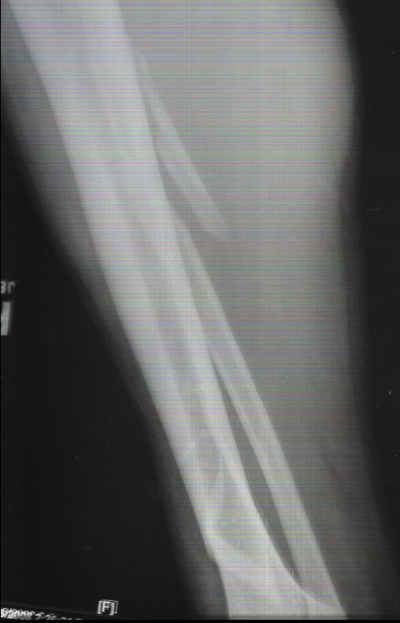

骨折圖片